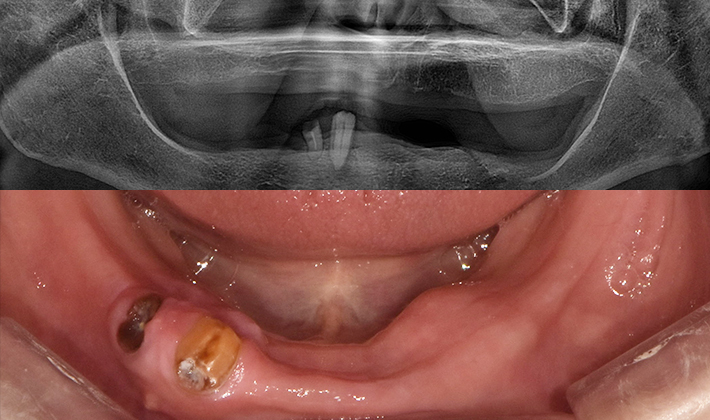

5060 시니어 임플란트

건강하고 오래가는 시니어 임플란트,

치료 사례부터 남다릅니다.

before

after

※ 위 임상사진은 동일조건으로 촬영되었으며, 사진에 대한 별도의 조작이 처리되지 않았습니다.

※ 위 임상사진 및 포트레이트는 환자와의 포괄적인 초상권 계약 이후 사용하고 있습니다.

※ 수술 및 치료과정에서 부작용이 발생할 수 있으므로 충분한 상담과 신중한 판단이 요구됩니다.